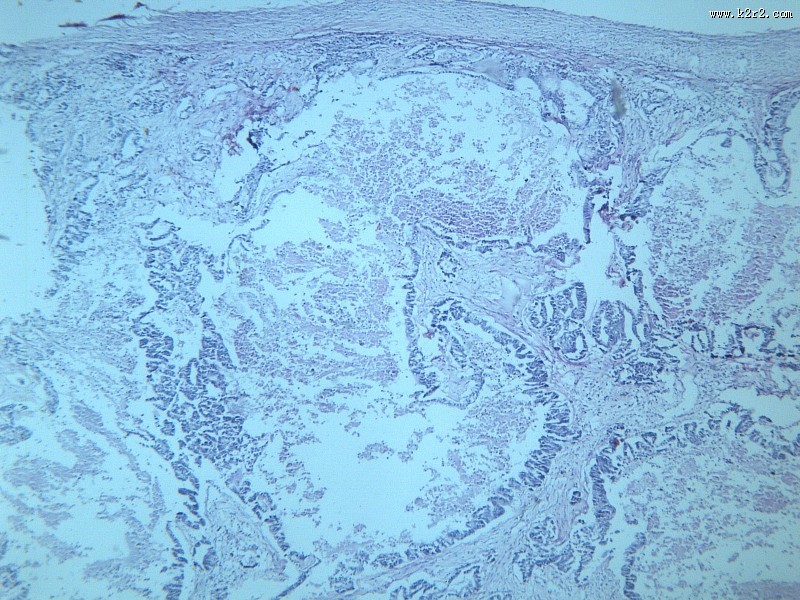

腺癌肝转移大全 - 第4张

腺癌肝转移大全

腺癌

腺癌肝转移